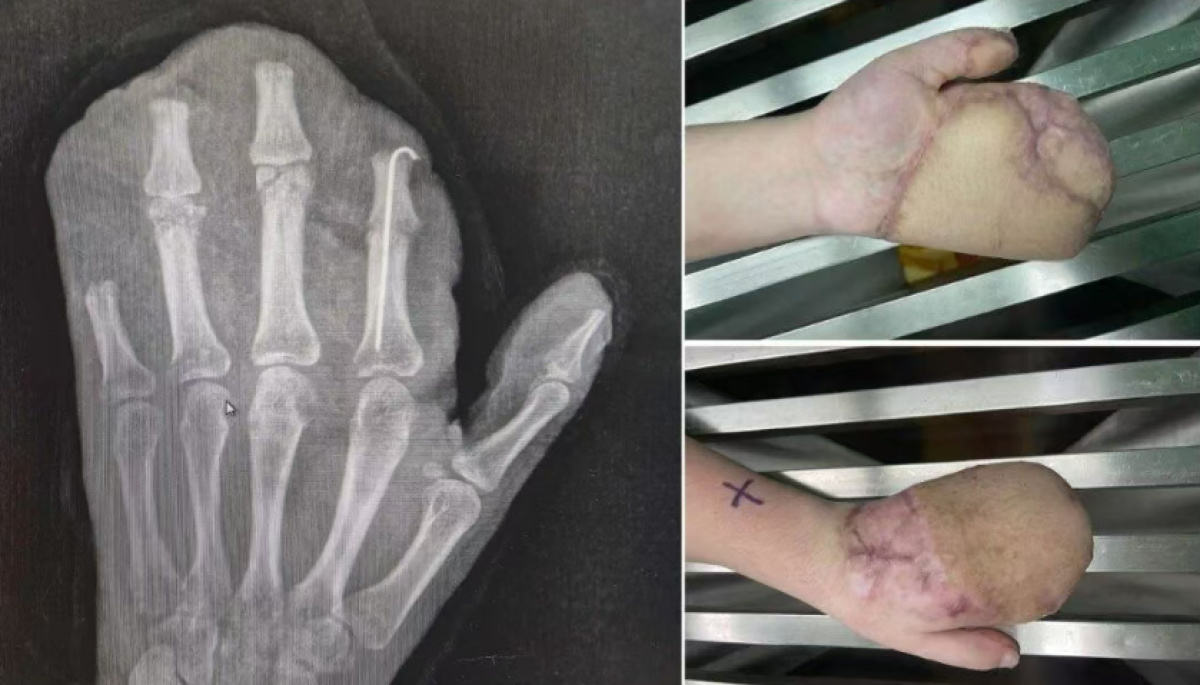

医生诊断他为:1.左手掌、手背,示指中指环指小指掌侧及背侧皮肤毁损脱套伤;2.左手掌、手背及各指肌腱神经血管损伤;3.左手多发性开放性指骨骨折伴毁损;4.左拇指末节指腹皮肤、软组织缺损;5.左拇指固有神经断裂;6.左拇指甲床裂伤。

为覆盖巨大创面,医生启用了经典的“腹部带蒂皮瓣”,将断手“寄养”在了带有自身血供的腹部皮肤上,为后续所有修复提供了生存的土壤。

经过近一个月的“腹手相连”,皮瓣在手部建立了新的血运。医生们进行了“断蒂”手术,让手从腹部独立,患者也获得了活动自由,为功能锻炼打下基础。

等待皮瓣完全稳定后,医生们开始了功能重塑。手术将臃肿的皮瓣进行修薄塑形,并进行了首次分指术,把粘连在一起的手指分开,同时取出了已愈合的骨折内固定物。

完美的指蹼(手指间的缝隙)是手指灵活张开与并拢的关键。为进一步改善外观与功能,今年1月11日,医院为他实施了二次分指与指蹼重建术,使用更精密的局部皮瓣,重建出更自然、更深的指蹼,让每根手指都能更独立。